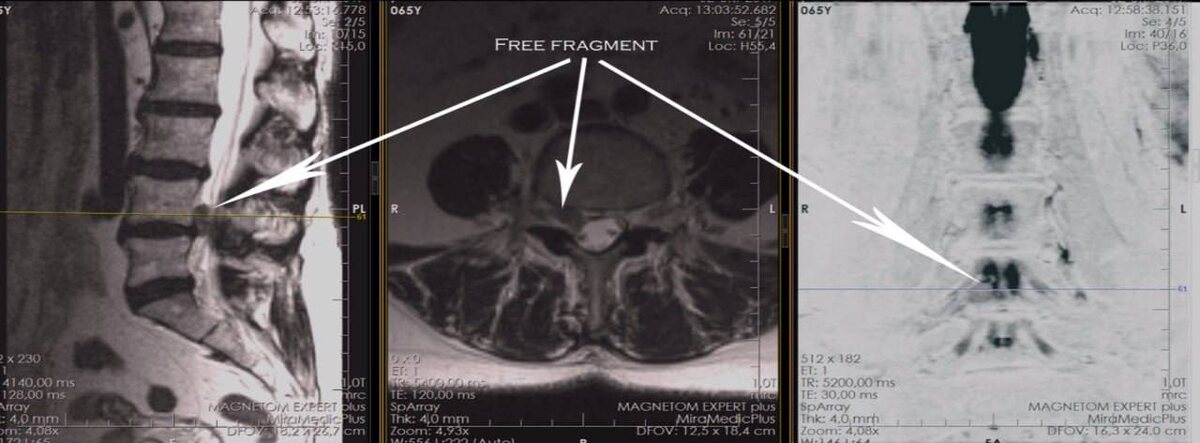

На фото изображено МРТ из практики Василия Королишина.

Принцип основан на действии магнитных полей, которые создают максимально четкие и информативные снимки, позволяющие поставить диагноз с высокой точностью.

Ко мне обратилась девушка на 7-м месяце беременности с острой болью в спине, ягодице и ноге. Срок большой. Но обследование необходимо. Мы провели МРТ, которое показало, что у пациентки дегенеративный стеноз позвоночного канала и радикулопатия.